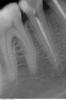

SergioS Опубликовано 14 февраля, 2013 Поделиться Опубликовано 14 февраля, 2013 Прошу помощи разобраться:Пациентка была у терапевта:30.01.- орто,44 под витапекс, временная пломба. перкуссия 44 болезненна2.02. - осмотр болит меньше.9.02 - боли усилились перкуссия 45 резко болезненна, 45 под Vitapex. Амоксиклав.12.02. - мой прием: Из анамнеза 3 дня назад перенесенная ветрянкатемпературы нет, ассиметрия лица(отек щечной области справа), гиперемии кожн покровов нет. Слизистая в области 46-43 со щечной сторны гиперемирована.отечна, флуктуации нет. 46 - подвижность 0-I степени. Перкуссия 46,45.44,43 резко болезненна. Что предпологаете? Мне еще корни 46 не нравятся(короткие они(я понимаю.что Попова-Годона). Ссылка на комментарий

johniola Опубликовано 14 февраля, 2013 Поделиться Опубликовано 14 февраля, 2013 обратите внимание на 47 Ссылка на комментарий

Большой Зеленый Опубликовано 14 февраля, 2013 Поделиться Опубликовано 14 февраля, 2013 44 причина. Чего мудрить то? насчет корней 46 ничего не понял. Чем они вам не нравятся? Откуда какой Попова-Годона? Ссылка на комментарий

johniola Опубликовано 14 февраля, 2013 Поделиться Опубликовано 14 февраля, 2013 либо у меня на компе искажается видимость либо я уже не вижу,но на 47 ламина сдохла Ссылка на комментарий

SergioS Опубликовано 14 февраля, 2013 Автор Поделиться Опубликовано 14 февраля, 2013 44 причина. Чего мудрить то? насчет корней 46 ничего не понял. Чем они вам не нравятся? Откуда какой Попова-Годона?Корни 46 короче, чем 47 и 36. Зубо-альвеолярное выдвижение(попова-годона) присутствует на 46. Ссылка на комментарий

johniola Опубликовано 14 февраля, 2013 Поделиться Опубликовано 14 февраля, 2013 попова -годона есть на 27 а на 46 не вижу Ссылка на комментарий

DoctorN Опубликовано 14 февраля, 2013 Поделиться Опубликовано 14 февраля, 2013 Терапевт тот же сейчас тока пошел открывать эти оба два зуба.витапекс,если мне не изменяет память-это плотная масса с гидроокисью кальция.в некоторых случаях авторы инструкции предлагают обтурировать им канал на постоянку.по первоначальному снимку дохлый,причем прилично,44,и скорее всего уже начались явления эксудации в периапикальном пространстве.канал обтурируется витапексом-отток нет(а если еще туда терапевт протолкнул файлом кусочек сдохшего нерва-между нами-)вот и результат.на мой взгляд с 6м и 7м все в порядке Ссылка на комментарий